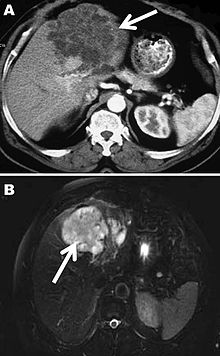

Computed tomography (A) and magnetic resonance (B) images of the liver of a 72-year-old man from French Guiana with polycystic echinococcosis affecting the left side of the liver. White arrows indicate the multicystic liver lesion.

A formal diagnosis of any type of echinococcosis requires a combination of tools that involve imaging techniques, histopathology, or nucleic acid detection and serology. For cystic echinococcosis diagnosis, imaging is the main method—while serology tests (such as indirect hemagglutination, ELISA (enzyme-linked immunosorbent assay), immunoblots, or latex agglutination) that use antigens specific for E. granulosus verify the imaging results. The imaging technique of choice for cystic echinococcosis is ultrasonography, since it is not only able to visualize the cysts in the body's organs,[30] but it is also inexpensive, non-invasive and gives instant results.[31] In addition to ultrasonography, both MRI and CT scans can and are often used although an MRI is often preferred to CT scans when diagnosing cystic echinococcosis since it gives better visualization of liquid areas within the tissue.[30][32]

Similar to the diagnosis of alveolar echinococcosis and cystic echinococcosis, the diagnosis of polycystic echinococcosis uses imaging techniques, in particular ultrasonography and CT scans, to detect polycystic structures within the person's body. However, imaging is not the preferred method of diagnosis since the method that is currently considered the standard is the isolation of protoscoleces during surgery or after the person's death, and the identification of definitive features of E. oligarthrus and E. vogeli in these isolated protoscoleces. This is the main way that PE is diagnosed, but some current studies show that PCR may identify E. oligarthrus and E. vogeli in people's tissues.[33] The only drawback of using PCR to diagnose polycystic echinococcosis is that there aren't many genetic sequences that can be used for PCR that are specific only E. oligarthrus or E. vogeli.[19]